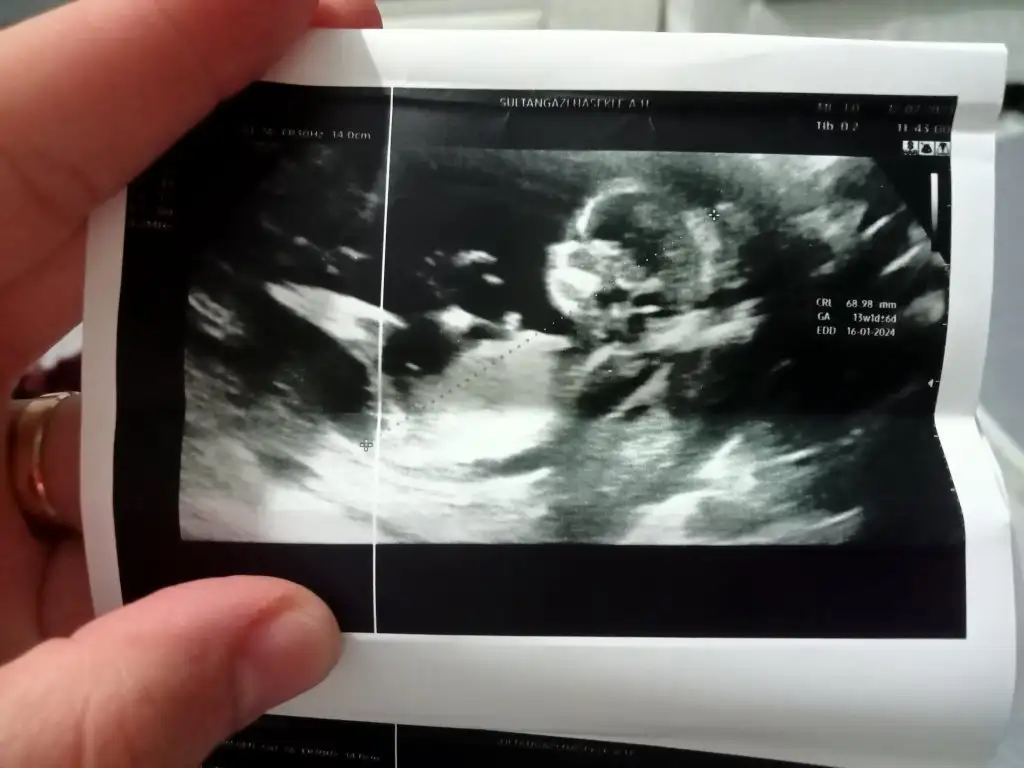

12+2 sizce cinsiyeti ne kızlar 🥰

Eklentiler

• IMG_1392.webp

IMG_1392.webp

20,9 KB · Görüntüleme: 35